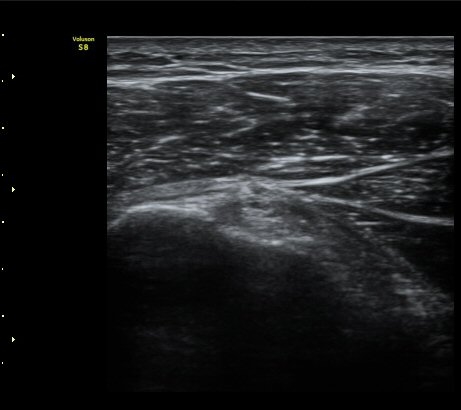

ÀÌµÎ¹Ú±Ù°Ç È¾´Ü¸é°Ë»ç¿¡¼­ ƯÀÌ ¼Ò°ßÀ» º¸ÀÌÁö ¾ÊÀ½(»çÁø 1, 2).

±Ø»ó°Ç Á¾´Ü¸é°Ë»ç¿¡¼­ ´ë°áÀý°ú »ó¿Ï°ñµÎ ÀÌÇàºÎÀ§¿¡ ÇÇÁú°ñ ¿¬¼Ó¼º ¼Ò½ÇÀ» º¸ÀÓ(±×¸² 3, 4, 5)